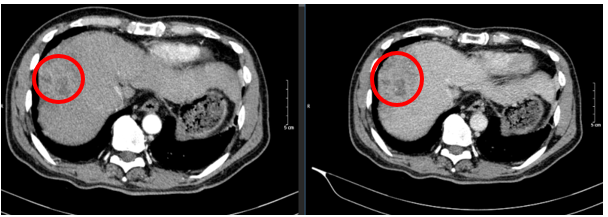

Ngày 27/02/2024: (sau 3 chu kì)

Hình 3: Hình ảnh chụp cắt lớp vi tính ổ bụng: U gan hạ phân thùy VIII (vòng tròn đỏ) kích thước 50x77mm, ngấm thuốc không đều, có thải thuốc sau tiêm sau điều trị, còn tăng sinh mạch, không có huyết khối

Ngày 19/06/2024: (sau 7 chu kì)

Hình 4: Hình ảnh chụp cắt lớp vi tính ổ bụng: Nhu mô vùng ngoại vi sát bao gan hạ phân thùy VII – VIII có đám (vòng tròn đỏ) giảm tỉ trọng kích thước ~ 28x36mm, trong có lắng đọng vật liệu nút mạch, không có huyết khối